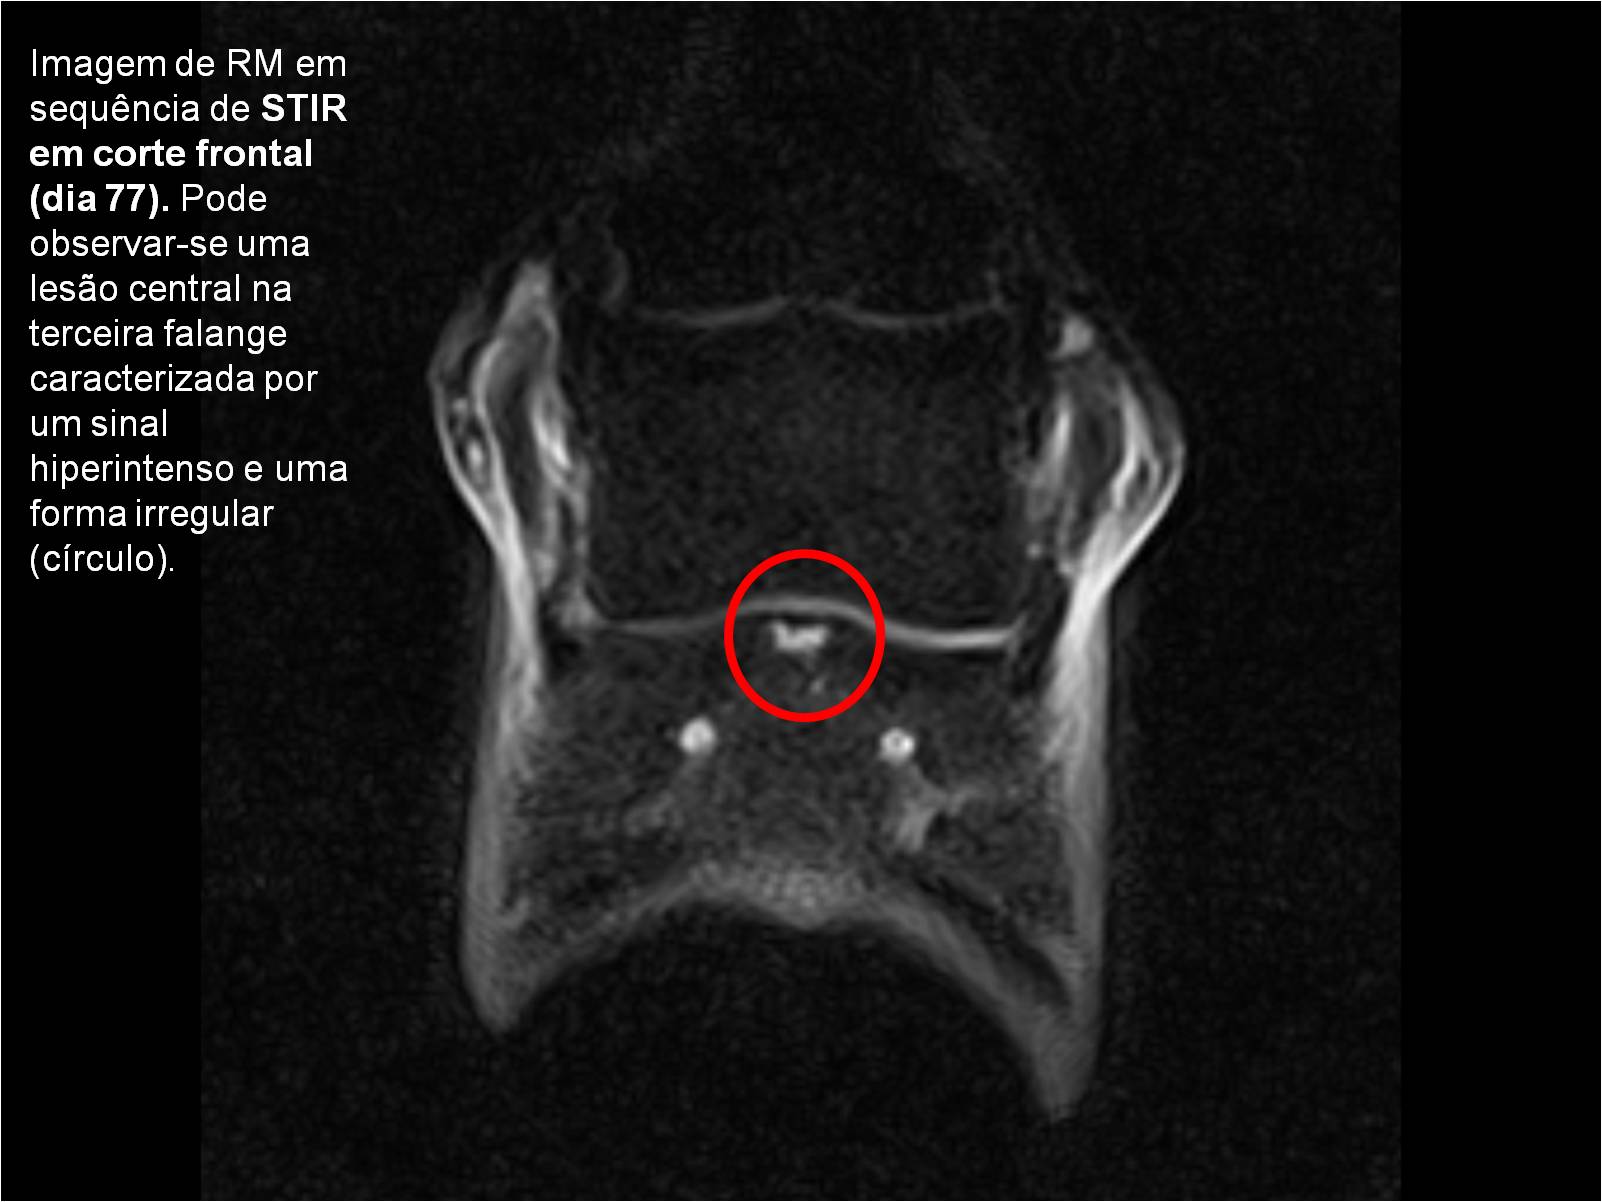

Publisher: Universidade de Évora

Abstract: O relatório de estágio encontra-se estruturado em três partes distintas. A primeira parte faz a caracterização das infraestruturas e funcionamento do Hospital Veterinário de Equinos de Lüsche, Oldenburg, Alemanha, assim como a análise casuística dos casos clínicos acompanhados durante os 6 meses de estágio. A segunda parte consiste de uma revisão bibliográfica sobre quistos do osso subcondral em equinos. Por fim, a terceira parte consta da apresentação e discussão de um caso clínico, nomeadamente o diagnóstico e acompanhamento imagiológico, por ressonância magnética, de um quisto subcondral na terceira falange num cavalo adulto; ### Abstract Equine Practice- Subcondral bone cyst of the third phalanx This internship report is divided in three parts. The first part characterizes the infrastructure and function of the Equine Hospital Lüsche, Oldenburg, Germany, as well as the casuistic of the clinical cases accompanied during the 6 month internship. The second part consists in a bibliographic review of cystic lesions of the subchondral bone in equines. The third part consists in a case report, the diagnostic and imagiological accompaniment, by use of magnetic resonance imaging, of a subchondral bone cyst in the distal phalanx of an adult equine.